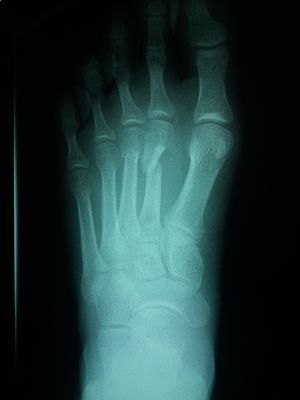

Emergency case

Fracture

Radiology

Foot

It is a stress fracture ??